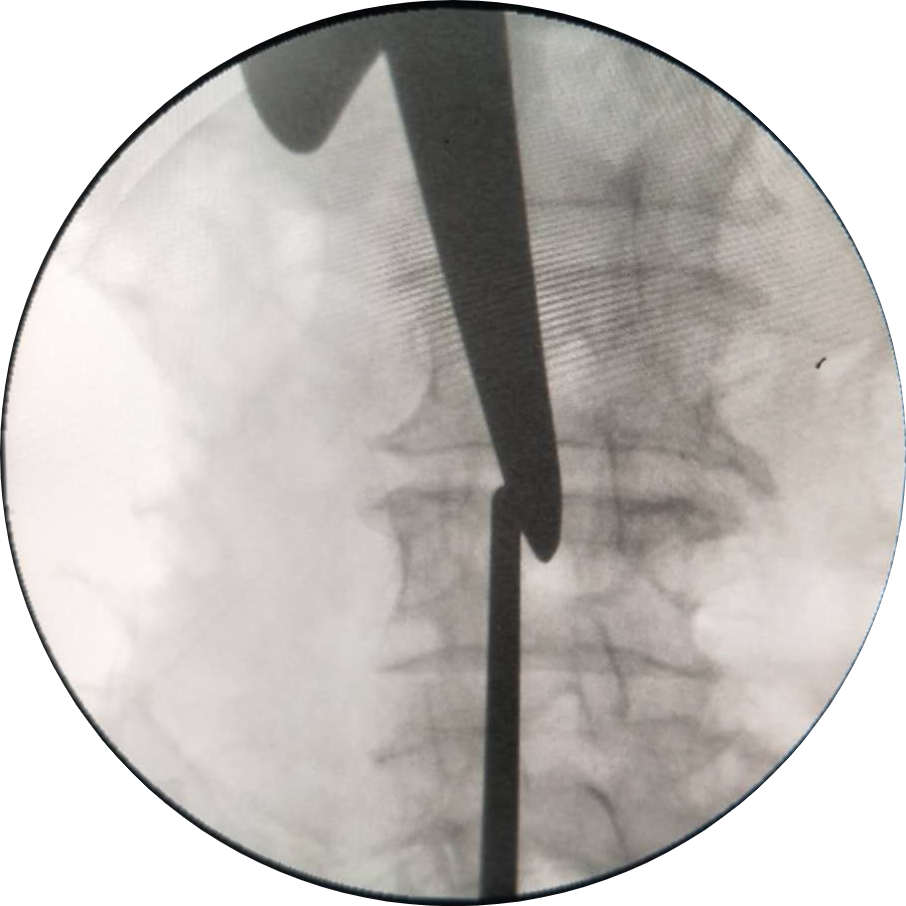

術前

(圖示:術前手術定位)

(圖示:通道準確植入目標間隙)